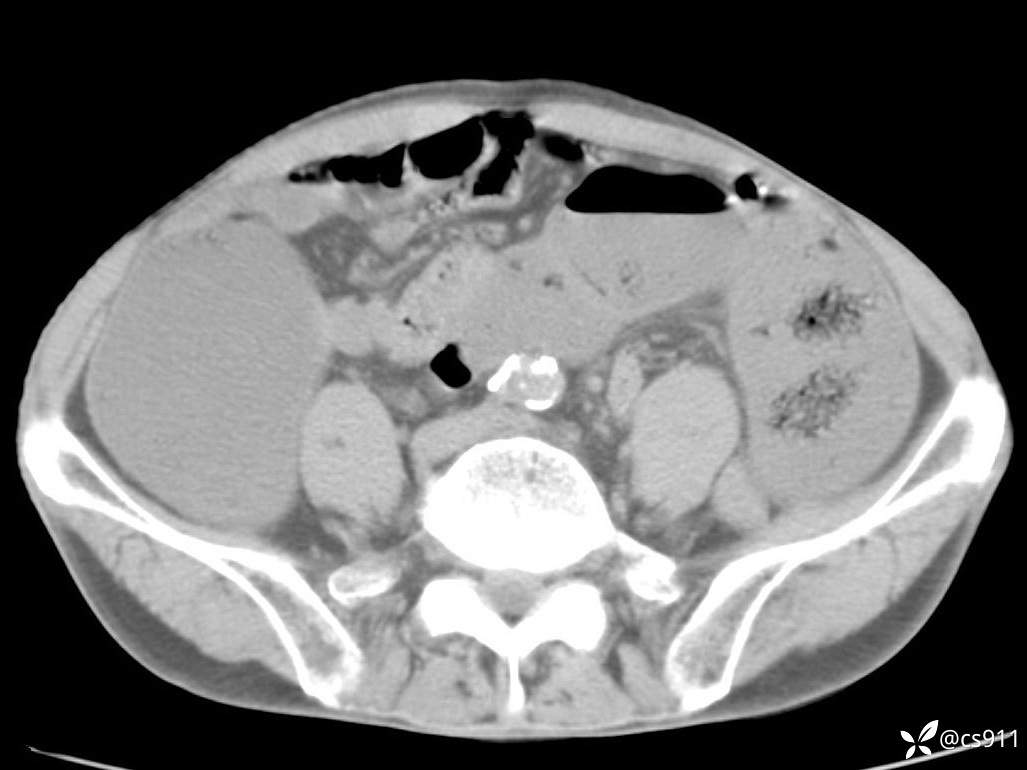

急腹症之急诊CT,原因?答案公布

男,77岁,腹痛、腹胀伴恶心呕吐1天。呕吐胃内容物,非喷射性呕吐,有咖啡色样胃内容物,诉有胃穿孔病史。查体:全腹平,下腹部压痛,全腹无反跳痛,叩诊呈浊音,移动性浊音阴性,肠鸣音减弱,1-2次/分。肛检:直肠未扪及明显肿物,可触及大量粪块。

T 36.6℃ P 80次/分 R 26次/分 BP 100/60mmHg

白细胞(WBC) H 14.55 10e9/L 4-10

中性粒细胞百分率(NEUT%) H 85.7 % 40-75

血淀粉酶(AMY) HH 1859 U/L 35-135

癌胚抗原(CEA) H 27.44 ng/ml 0-5

呕吐物 潜血试验 * 阳性 阴性

患者轮椅入室检查神志清楚, 能配合摆位和呼吸